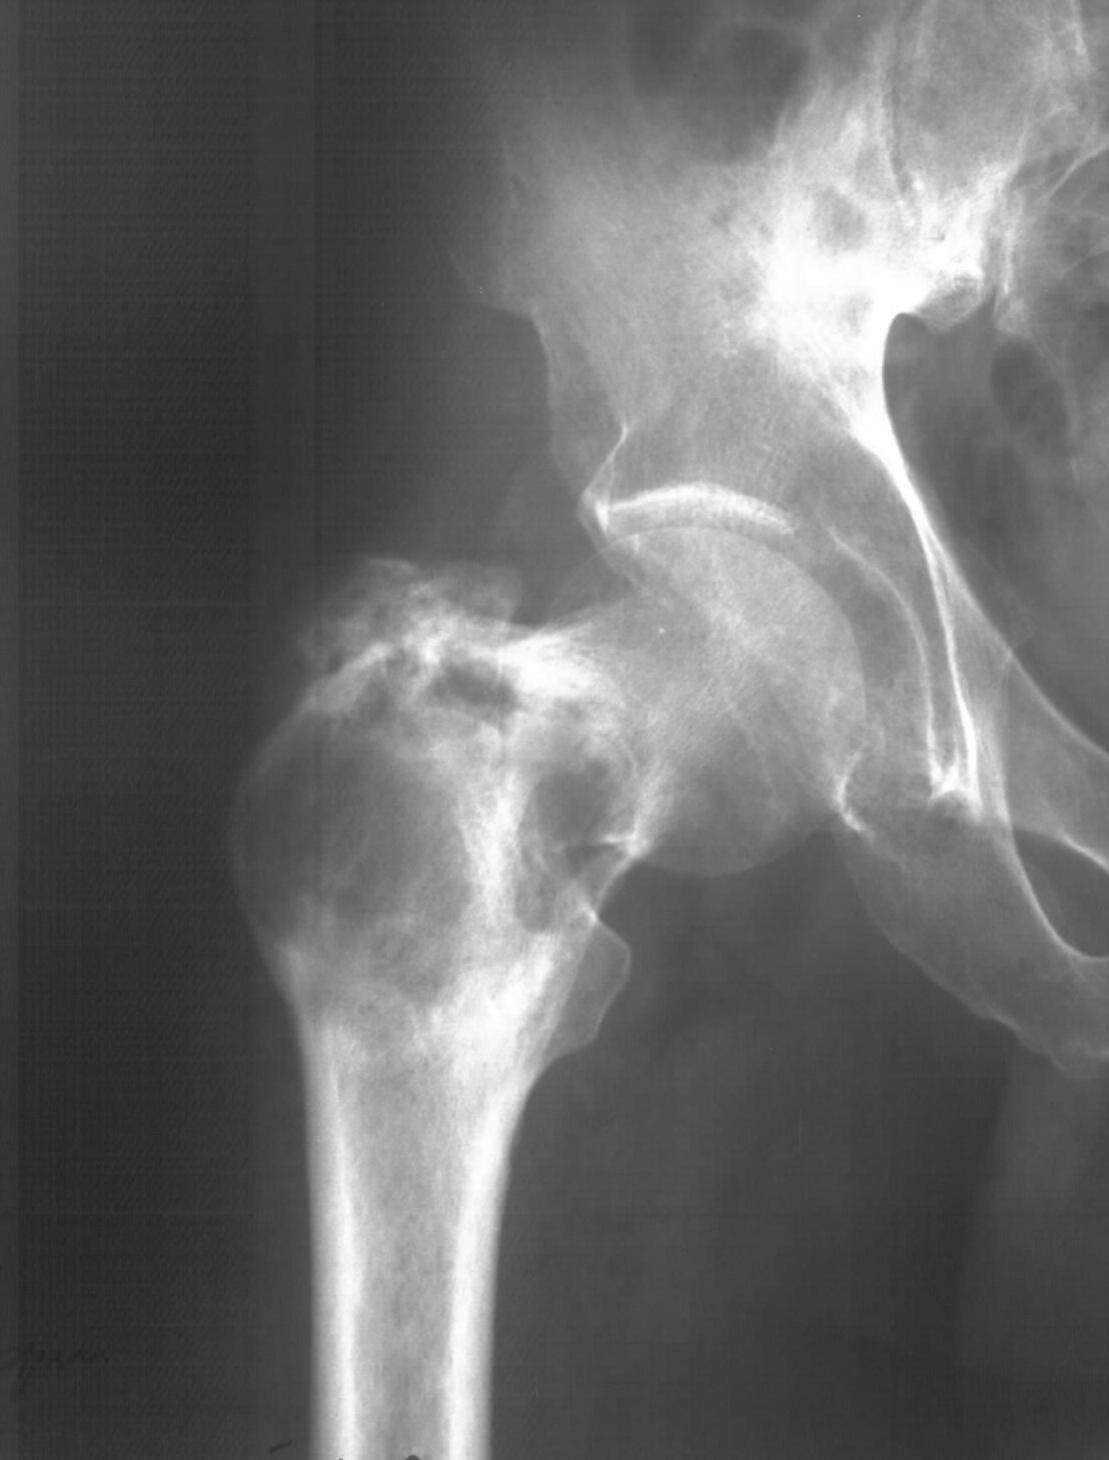

Диагноз: Ангиосаркома проксимального отдела правой бедренной кости. Патологический перелом шейки бедренной кости. Множественные метастазы в легкие, позвоночник, ребра, кости таза.

31.05.09 упал дома с высоты собственного роста. Появились сильные боли в правом тазобедренном суставе. Самостоятельно обратился в ГУЗ «СККЦ СВМП». При клиническом обследовании и рентгенографии был диагностирован патологический перелом шейки бедренной кости.Объективно:

Имя     : Р-графия.JPG

Тип     : image/jpeg

Размер  : 78634 байтов

Описание: отсутствует

Url     : http://weborto.net:8080/pipermail/ortho/attachments/20090619/8925512e/attachment-0003.jpeg